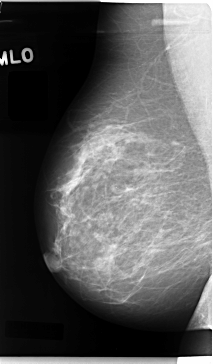

C_0059_1.RIGHT_MLO

RIGHT_MLO LINES 4720 PIXELS_PER_LINE 2768 BITS_PER_PIXEL 12 RESOLUTION 50 NON_OVERLAY